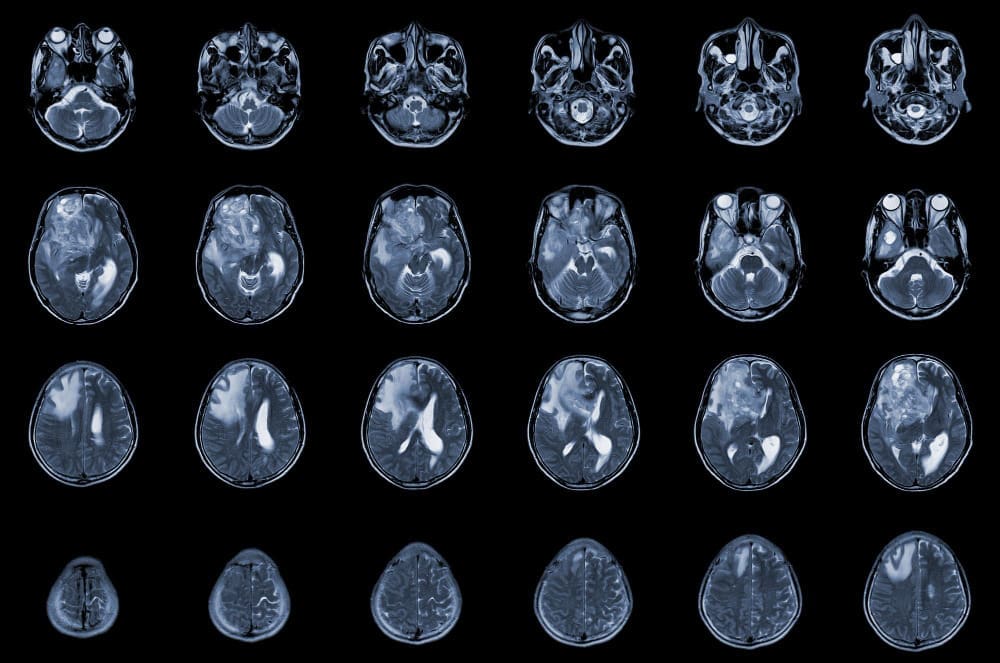

It’s important to have regular MRI scans to check the tumor’s size. Patients should know when to seek urgent medical help.

Long-term care is vital for benign meningioma patients. Regular check-ups and scans are needed to watch for tumor growth and any treatment side effects.

The timing of these visits can change based on the tumor and patient health. Usually, patients have MRI scans for years after surgery.